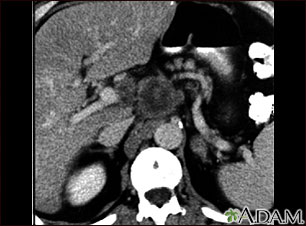

Esta TC de la parte superior del abdomen muestra un tumor (carcinoma pancreático) en la cabeza del páncreas que se puede observar en el medio de la imagen.